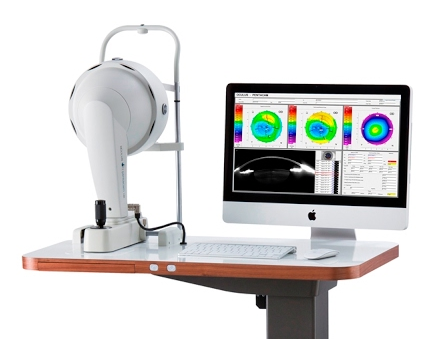

O diagnóstico do ceratocone é feito por meio de exames específicos que analisam a curvatura, a espessura e a integridade da córnea. Entre os principais exames estão:

- Topografia corneana: mapeia a superfície da córnea e detecta áreas de protrusão e irregularidades.

- Tomografia de córnea (Pentacam ou Galilei): fornece uma visão tridimensional da córnea e permite avaliar espessura, curvatura e elevações.

- Paquimetria: mede a espessura da córnea, essencial para identificar o afinamento característico da doença.

- Refratometria e Ceratometria: ajudam a avaliar o grau de astigmatismo irregular.

- Biomicroscopia: permite observar sinais clínicos do ceratocone em lâmpada de fenda.

Com esses exames, é possível identificar o ceratocone mesmo antes que os sintomas se tornem evidentes, permitindo traçar o plano de tratamento mais adequado.